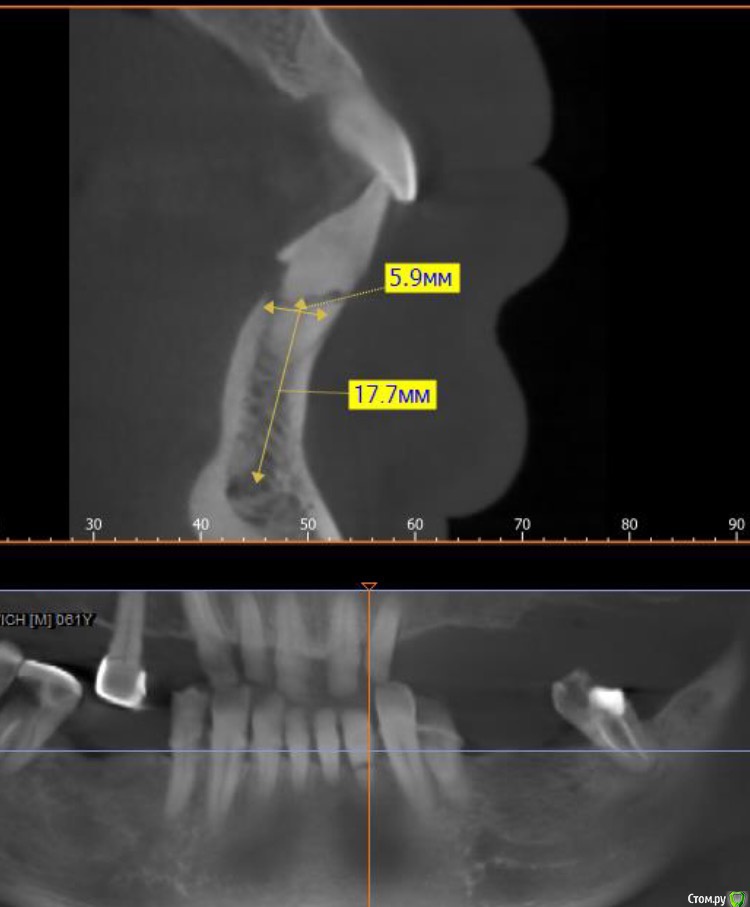

carloss Опубликовано 20 декабря, 2015 Поделиться Опубликовано 20 декабря, 2015 ну ок, один плох.. ну пусть ещё соседний.. ну пусть все резцы(во что я лично не верю, покажи рентген, можем поговорить про подвижность)) Но зачем клыки убирать, премоляр?.. и лишать пациента остатков тактильной чувствительности со всеми вытекающими минусами подков на имплантатах? даже судя по тем крохам КТ, которые ты показал, там даже количество имплантатов бы не увеличилось.. и наверное даже без нкр.. а так, конечно получилось, ты бы еще зигомы воткнул, а чё))? 1 Ссылка на комментарий